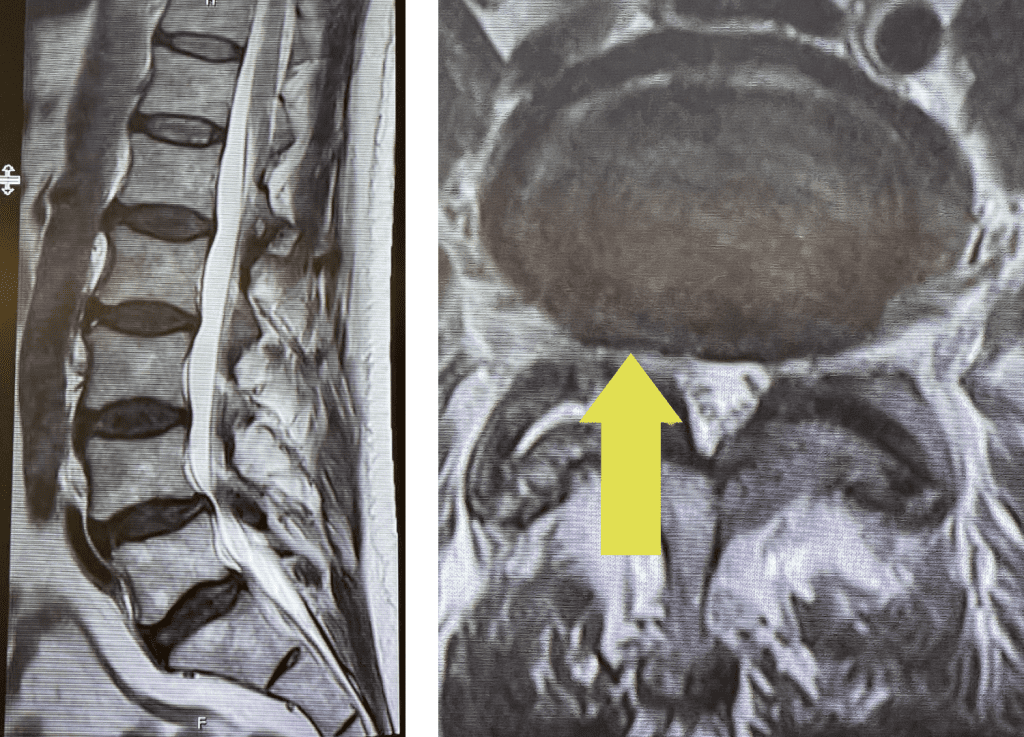

Fig 1: Sagittal and axial T2-weighted lumbar MRI demonstrating severe L4-5 Stenosis and grade 1 spondylolisthesis. Note (yellow arrow) cystic anteromedial extension off the right facet joint causing right-sided lateral recess cut-off of thecal sac and compression of the right L5 nerve root.

This 70 year-old male with two years of right leg pain with minimal low back pain. The patient had tried physical therapy and epidural injections. Neurologically he was intact. MRI revealed a grade 1 spondylolisthesis (slipped spine in Greek) at L4-5 with severe lumbar stenosis mainly due to thickened yellow ligament and overgrown joints; but the thing that I believe put him over the edge was a small joint cyst on the right (Fig 1). People just form cysts. You can get a cyst in practically every organ including kidney, liver, ovarian, etc. People are actually fascinated by them. When patients have spine surgery the only thing that matters to them is, “did you get the cyst?” The fact is that they are these small gelatinous balls that come off the joint space and grow into the spinal canal and cause symptoms by compressing the nerve. You essentially bite them away with our instruments. You really can’t aspirate them through the skin. They are just a form of arthritis and are always benign.